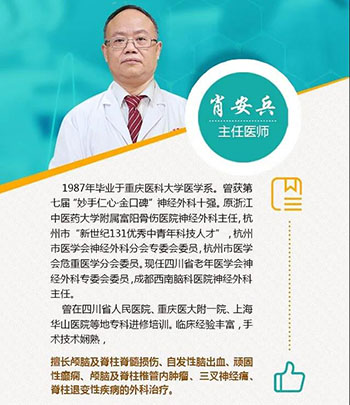

我院神经外科肖安兵主任温馨提醒

眼睑下垂、动眼神经麻痹的病人切不可大意,要先排除较凶险的脑动脉瘤。当然,还有脑部和眼眶肿瘤、动眼神经炎、糖尿病、脑梗塞等,也可能造成动眼神经麻痹,但这些情况都没有脑动脉瘤凶险。